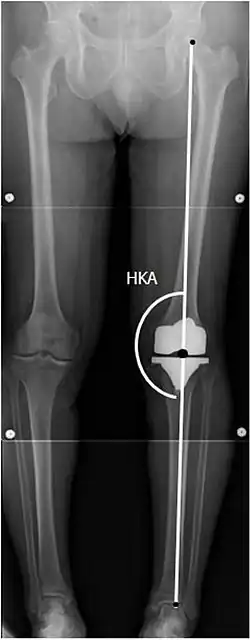

To indicate knee replacement in case of osteoarthritis, its radiographic classification and severity of symptoms both should be substantial. Such radiography should consist of weightbearing X-rays of both knees: AP, lateral, and 30 degrees of flexion. AP and lateral views may not show joint space narrowing, but the 30-degree flexion view is most sensitive for narrowing. Full-length projections also are used in order to adjust the prosthesis to provide a neutral angle for the distal lower extremity. Two angles used for this purpose are:

- Hip-knee-shaft angle (HKS),[10] an angle formed between a line through the longitudinal axis of the femoral shaft and its mechanical axis, which is a line from the center of the femoral head to the intercondylar notch of the distal femur.[12]

- Hip-knee-ankle angle (HKA),[11] which is an angle between the femoral mechanical axis and the center of the ankle joint.[12] It is normally between 1.0° and 1.5° of varus in adults.[13]

Knee replacement is routinely evaluated by X-ray, including the following measures:

![HKA: Hip-knee-ankle angle, which is ideally between 3° varum to 3° valgum from a right angle.[62]](./_assets_/X-ray_of_HKA_angle_with_knee_prosthesis.jpg)